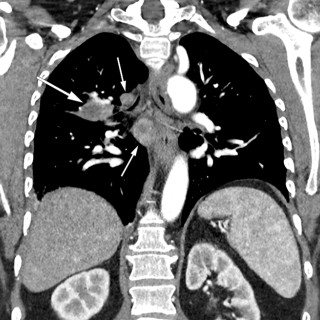

Lungesykdommer